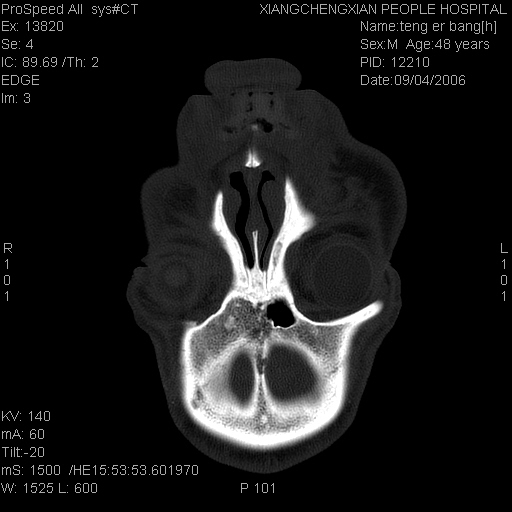

患者,男,以头面部外伤后头疼1小时为主诉入院,患者1小时前被他人打伤头部及左侧面部,眼睑无水肿,左侧面部肿胀压疼,未触及骨擦音。专科检查:耳鼻喉未见异常。

ct:平扫+冠扫:双侧鼻骨对比,冠扫s6#示右侧鼻骨尖部可见线状低密度影,边缘光滑,并见硬化.软组织未见肿胀.

诊断意见:鼻额缝(鼻骨与上颌骨额突缝),但个别同志认为是骨折.因此请同行们会诊.多谢了!